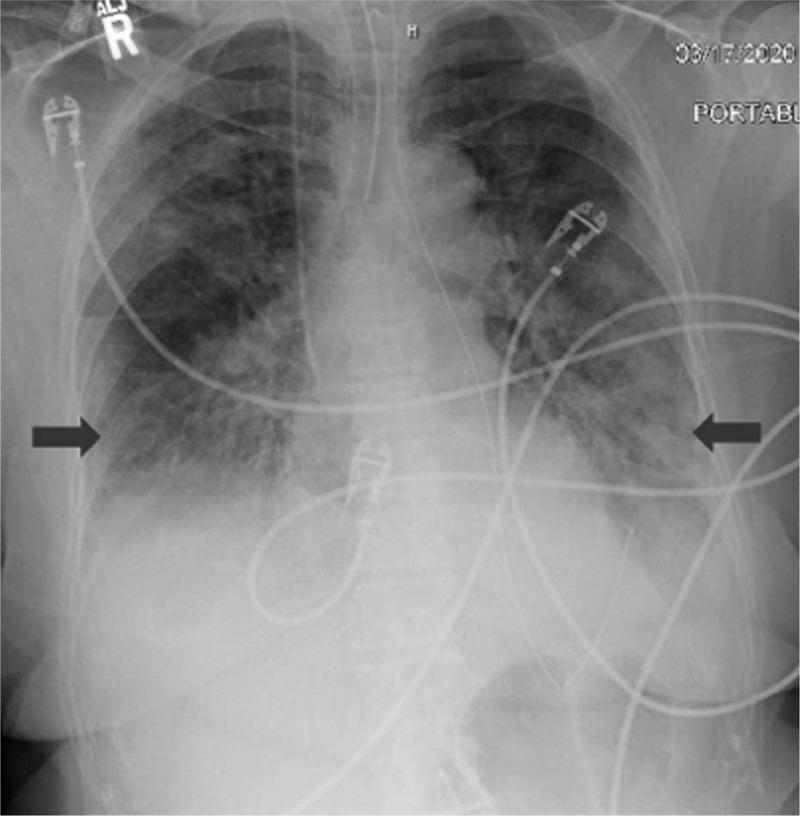

Chest X-rays revealed bilateral infiltrates worse at the lung bases and CT scan of the chest showed bilateral ground-glass opacities consistent with COVID-19. While our testing revealed a negative COVID-19 result at our institution, the result at a previous hospital returned a positive result.

胸部X光显示双侧肺底部浸润更严重,胸部CT扫描显示双侧磨玻璃样混浊,符合COVID-19表现。虽然我院检测结果为COVID-19阴性,但之前就诊医院的检测结果为阳性。